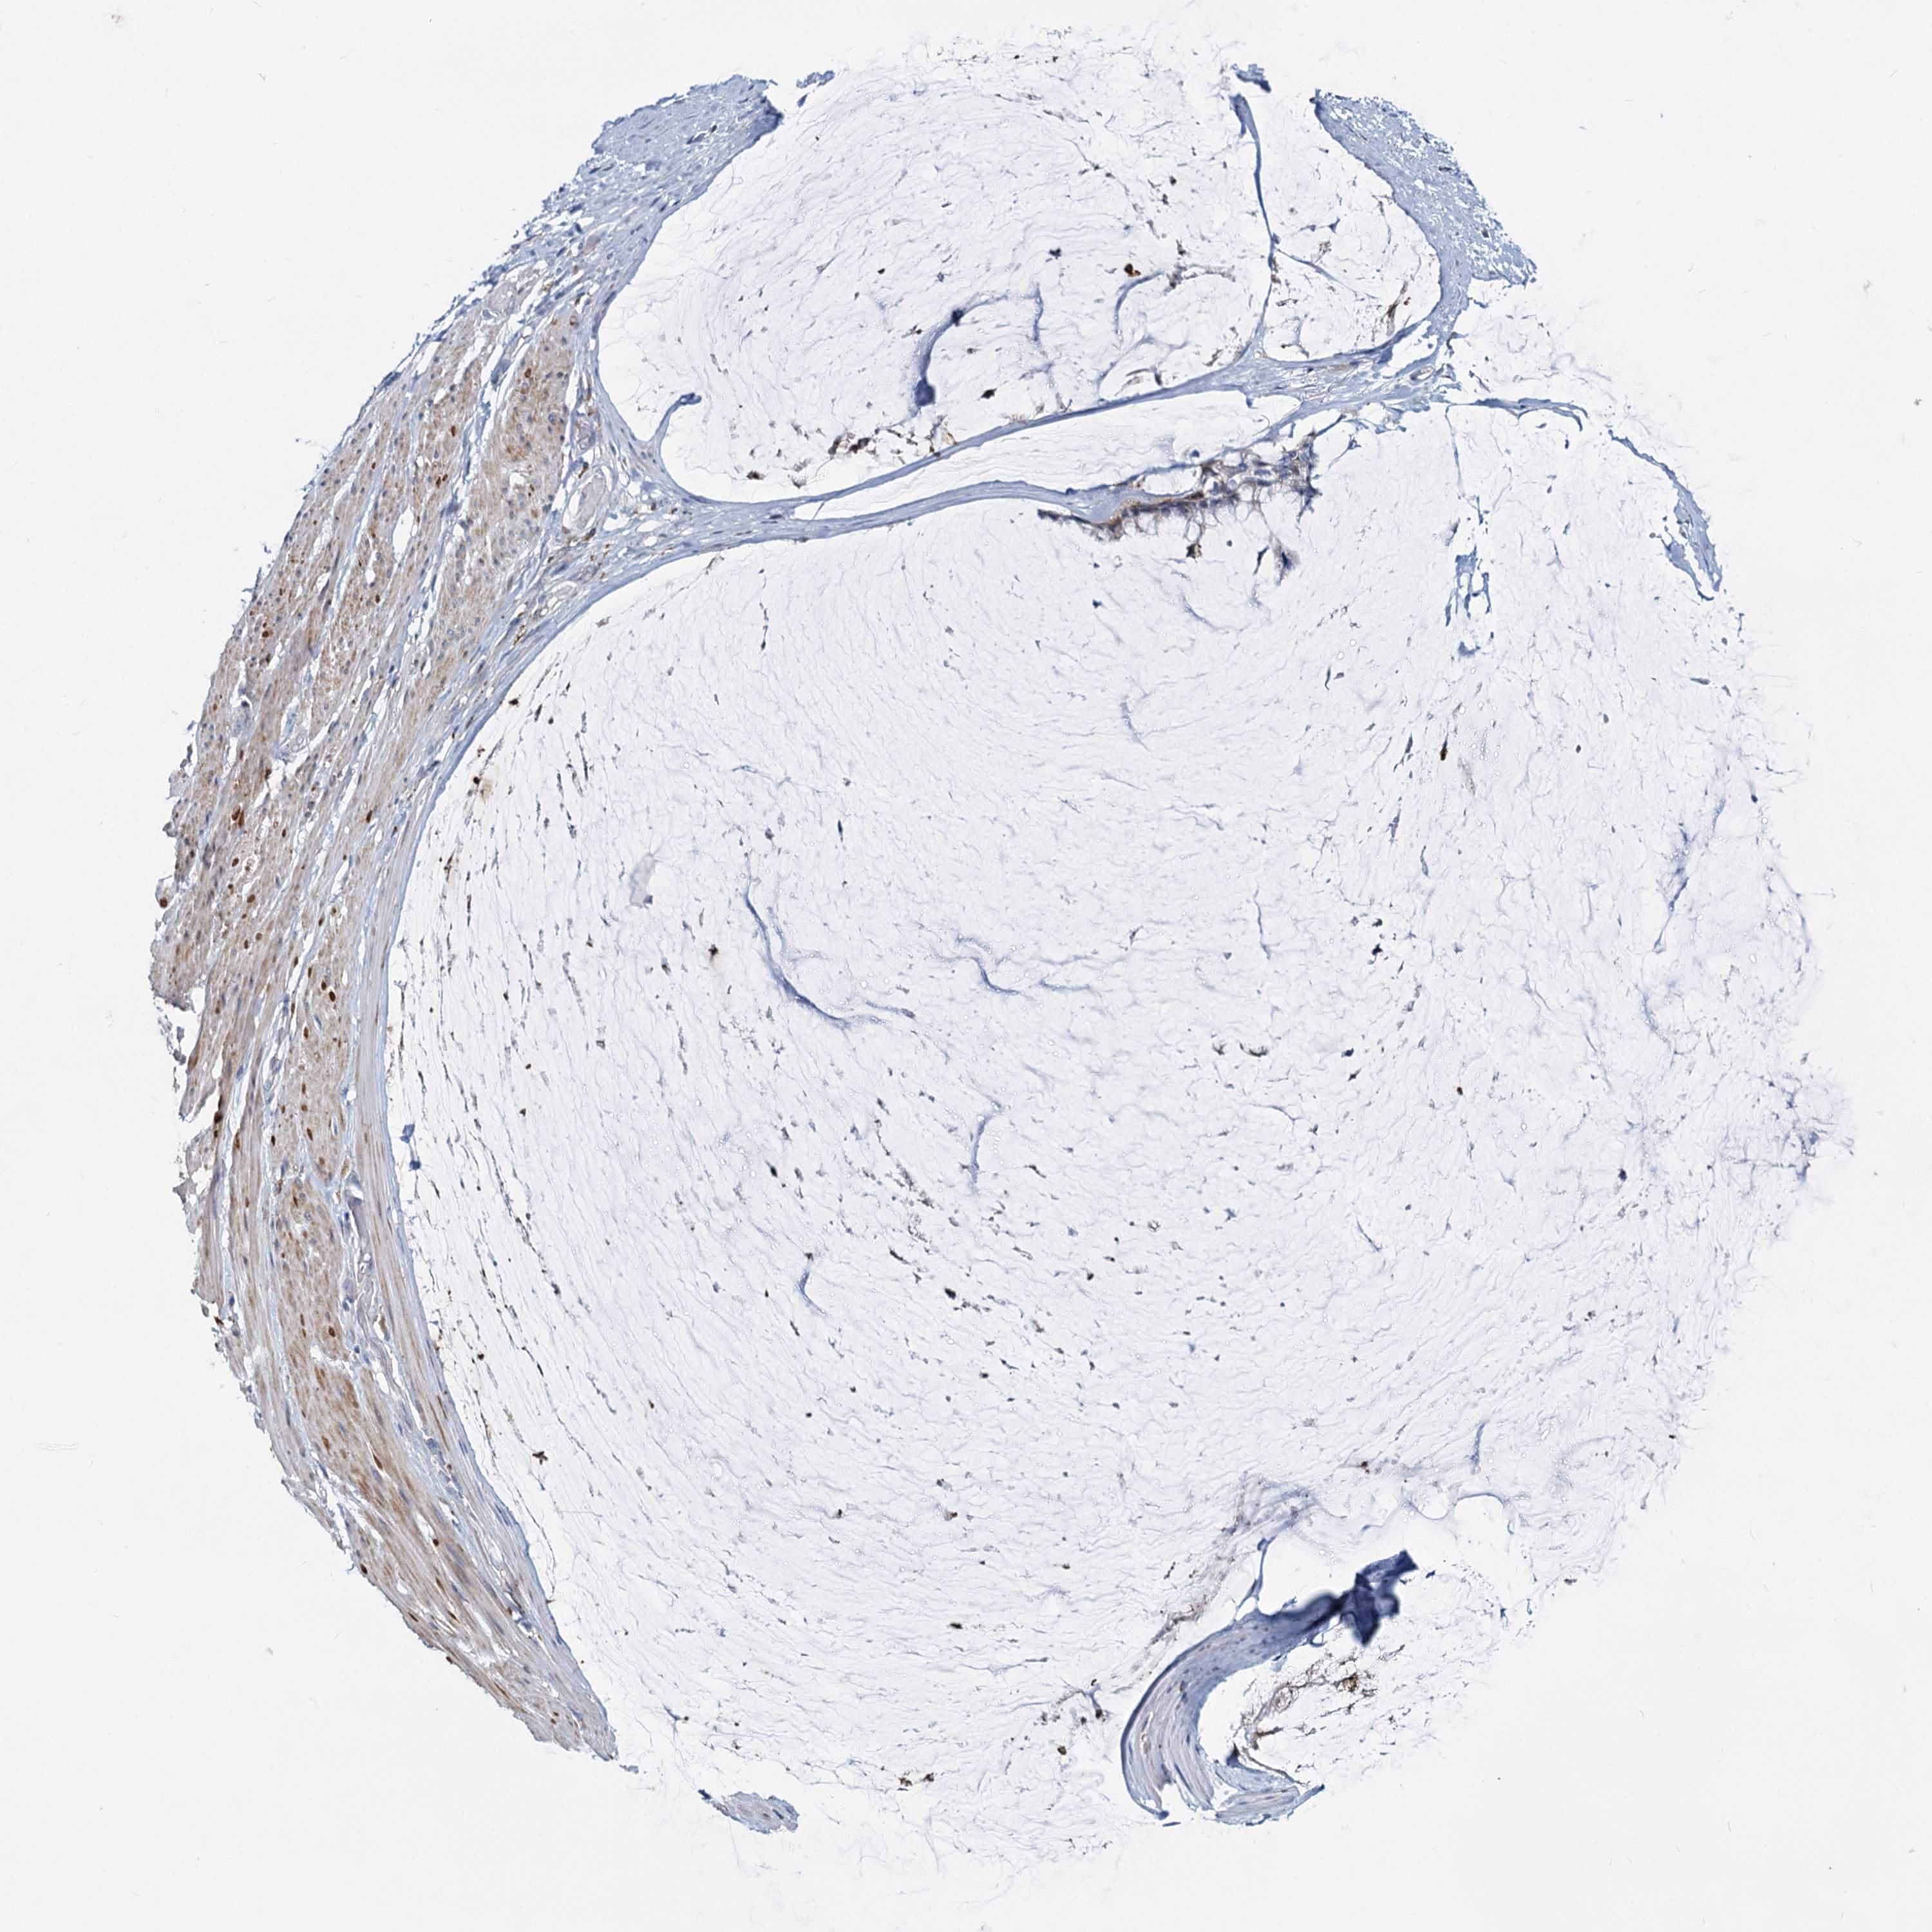

OVARIAN CANCER - Protein expressioni

A mouse-over function shows sample information and annotation data. Click on an image to view it in a full screen mode. Samples can be filtered based on level of antibody staining by selecting one or several of the following categories: high, medium, low and not detected. The assay and annotation is described here.

Note that samples used for immunohistochemistry by the Human Protein Atlas do not correspond to samples in the TCGA dataset.

Antibody stainingi

Antibody staining in the annotated cell types in the current human tissue is reported as not detected, low, medium, or high, based on conventional immunohistochemistry profiling in selected tissues. This score is based on the combination of the staining intensity and fraction of stained cells.

Each image is clickable and will lead to virtual microscopy that enables deeper exploration of all samples and also displays staining intensity scores, fraction scores and subcellular localization as well as patient and tissue information for each sample.

Antibody HPA039349

Staining

High

Medium

Low

Not detected

Intensity

Strong

Moderate

Weak

Negative

Quantity

>75%

75%-25%

<25%

None

Location

Nuclear

Cytoplasmic/membranous

Cytoplasmic/membranous,nuclear

Cystadenocarcinoma, serous, NOS

Carcinoma, endometroid

Cystadenocarcinoma, mucinous, NOS

Carcinoma, NOS